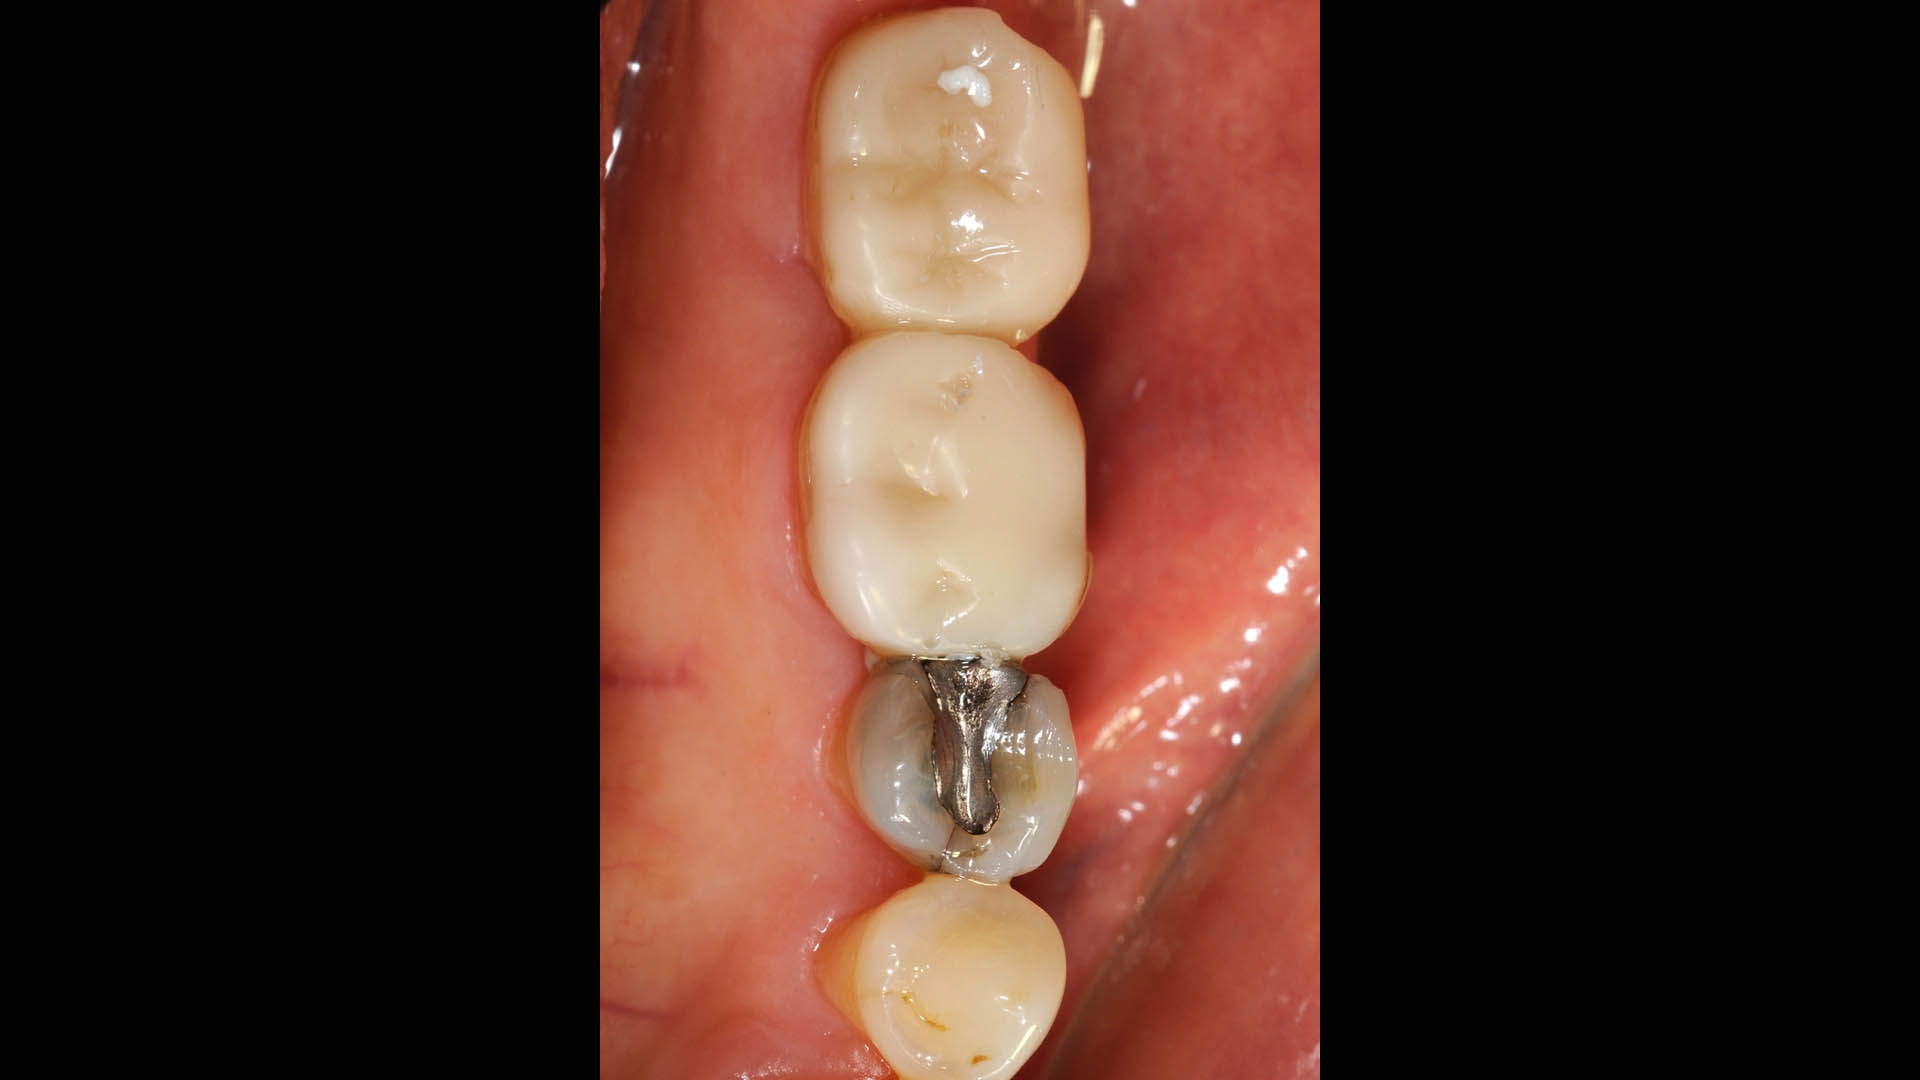

Take a glimpse into the magic of Coral Gables Dentistry through our before and after pictures. See firsthand the incredible smile makeover transformations that have brought confidence and joy to our patients.